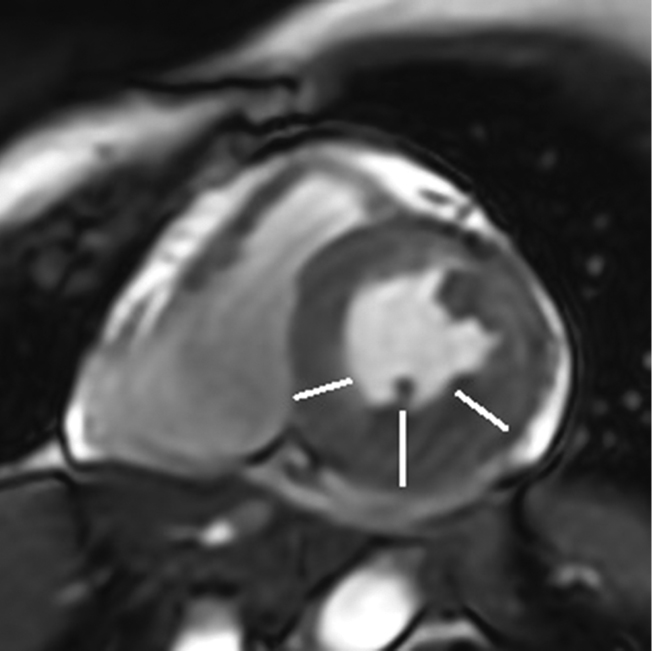

EchoCG was performed using modern technologies of three-dimensional image reconstruction and Mitral Valve Quantification model on Vivid-9 ultrasound device. The results showed that mitral regurgitation was mild [16]. The effective regurgitation orifice area was 0.18 cm2, and the regurgitation volume was 20 mL. Both mitral valve leaflets were myxomatous, thickened, and prolapsed up to 8 mm into the LA cavity (Fig. 1–3). The prolapse was polysegmental (Fig. 4). Signs of MAD (absence of myocardial tissue up to 9 mm under the posterior mitral valve leaflet) were revealed (Fig. 1, 2).

Fig. 1. Parasternal long-axis view of the left ventricle. Systole. White arrows indicate elongated and thickened mitral valve leaflets prolapsing into the left atrial cavity. The black arrow indicates the disjunction area

Fig. 2. Parasternal long-axis view of the left ventricle. Diastole. The elongated and thickened mitral valve leaflets (predominantly posterior) are visible. The black arrow indicates the disjunction area below the posterior mitral valve leaflet.

Fig. 3. Three-dimensional reconstruction of the mitral valve. The white arrow indicates the elongated and prolapsed mitral valve leaflets